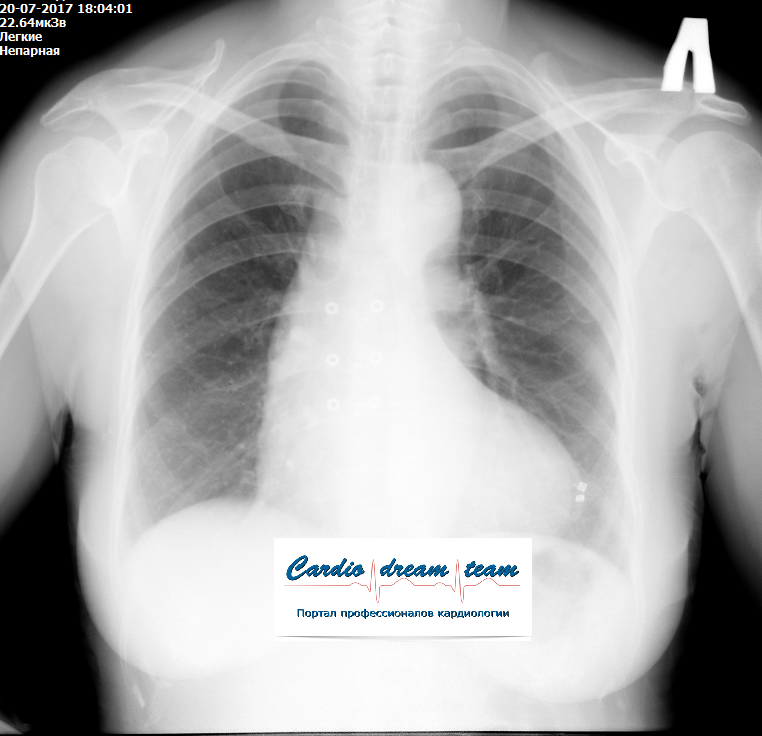

М, 69 лет. РАА. На первом снимке расширение срединной тени. На втором гемоторакс в результате прорыва крови из аорты в плевральную полость.